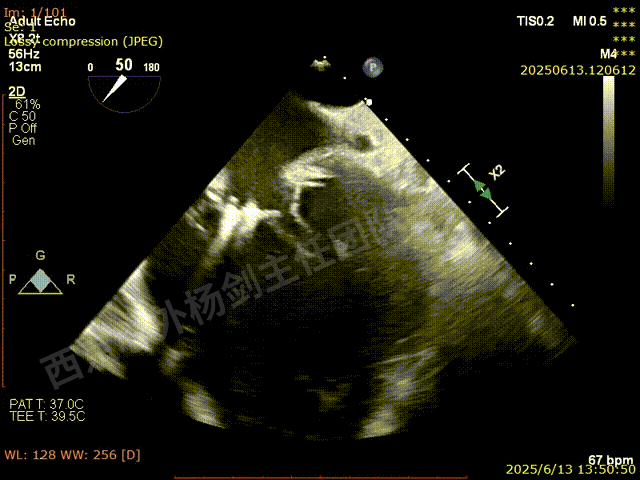

TAVR术后,全心增大,二尖瓣反流重度,三尖瓣反流重度。中量心包积液。左室严重增大,标准图像调整困难。主动脉瓣位带支架人工瓣膜瓣叶启闭正常,主动脉瓣位人工瓣上血流速度Vmax 148cm/s,PGmax 9mmHg,Vmean 86cm/s,PGmean 2mmHg, VTI 34.7cm,瓣周反流(轻)。估测肺动脉收缩压约49mmHg;左室收缩功能明显减低。LVEF:23%,EDV:364ml,ESV:221ml。

彩色血流示:二尖瓣反流缩流颈彩宽6.6mm,面积17cm²,容积30ml;二尖瓣瓣口面积6.6cm²,瓣环内径:左右径34mm,前后径34mm。2区瓣叶长度:前叶36mm,后叶20mm,叶环比1.6. 三尖反流面积17.2cm²,容积33ml,Vmax 291cm/s,PGmax 34mmHg。

TEER术前超声评估

二尖瓣后叶栓系严重,前叶相对错位,反流束沿2区分布广泛,2偏3区处存在反流。

反流宽度至少23mm,因影像调整困难,考虑实际反流更宽。